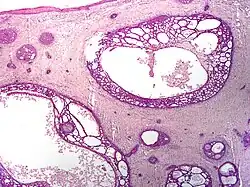

Micrograph of a basal-cell carcinoma, showing the characteristic histomorphologic features (peripheral palisading, myxoid stroma, artefactual clefting), H&E stain

Basal-cell carcinoma (BCC) is named after the basal cells that populate the lowest layer of the epidermis due to the histological appearance of the cancer cells under the microscope.[16] Nevertheless, not all BCCs originate within the basal layer.[16] Some are thought to develop from the folliculosebaceousapocrine germinative cells known as trichoblasts. Trichoblastic carcinoma is a term used to describe a rare and potentially aggressive malignancy that is also thought to arise from trichoblasts and may resemble a benign trichoblastoma (differential diagnosis can be challenging).[17][18][19] It has been suggested that lesions diagnosed as trichoblastic carcinoma may actually themselves be BCC.[20]

Nodular basal-cell carcinoma (also known as "classic basal-cell carcinoma") accounts for 50% of all BCC.[29] It most commonly occurs on the sun-exposed areas of the head and neck.[30]: 748 [31]: 646  Histopathology shows aggregates of basaloid cells with well-defined borders, showing a peripheral palisading of cells and one or more typical clefts.[29] Such clefts are caused by shrinkage of mucin during tissue fixation and staining.[32] Central necrosis with eosinophilic, granular features may also be present, as well as mucin. The heavy aggregates of mucin determine a cystic structure. Calcification may also be present, especially in long-standing lesions.[29] Mitotic activity is usually not so evident, but a high mitotic rate may be present in more aggressive lesions.[29] Adenoidal BCC can be classified as a variant of NBCC, characterized by basaloid cells with a reticulated configuration extending into the dermis.[29]